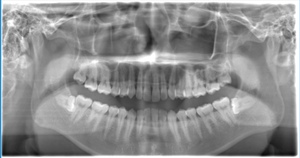

CASE 1

基本情報

| 年齢・性別 | 30代・女性 |

| 主訴 | 左右に分けて親知らずを抜きたい、できれば痛くなく抜きたい |

| 親知らずのはえ方 | 完全に出ていてまっすぐはえている |

| 抜歯期間 | 15分 |

| 抜歯費用 | 約2,000円(保険内) |

| 抜歯内容 |

何度か虫歯になり痛みはないが早めに抜きたい。 完全に頭が出ているため歯ぐきを切ったり骨を削らずに抜歯しました。 根の形も単純なため抜歯自体は5分もかからず上下ともに終わりました。 術後痛みや腫れも出ていません。 抜歯後は感染をしやすいため必ず抗生物質を飲み切ってください。 |